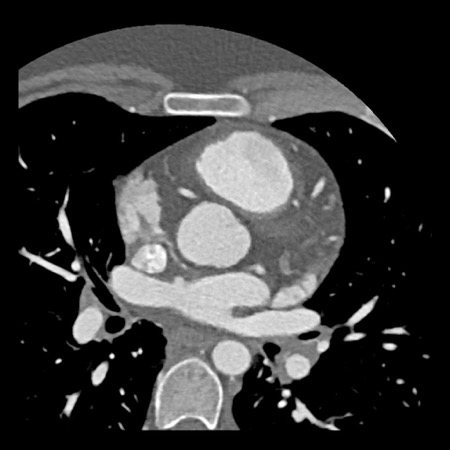

case 2 – CAD-RADS 5/P2/S

First, scroll through the CTA images.

How would you describe the findings on the coronary CTA?

The findings are:

- Stent in the mid

LAD with low-attenuation within the stent suggestive of minimal in-stent

restenosis (<25%). Non-calcified plaque distal to the stent

causing mild stenosis (25-49%). Notice bridging on a short segment in

the distal LAD. - Non-calcified

plaque in the LCX causing mild stenosis (25-49%). - Occlusion of the

proximal OM1 branch with distal filling. - Calcified and

non-calcified plaques in the proximal RCA causing mild (25-49%) stenosis. - Total plaque burden

is moderate based on SIS (four segments including proximal RCA, mid LAD, prox

LCX and OM1).

Due to the occlusion of OM1 branch and presence of the stent, this case

reads as CAD-RADS 5/P2/S, which means that this patient needs further

diagnostic workup.